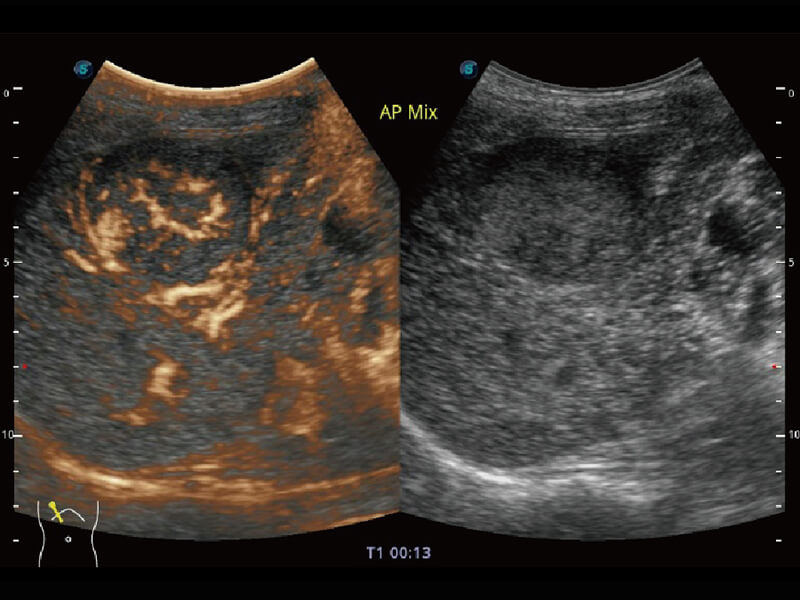

成像功能

性能优异的硬件架构,极大提升超声系统的运行效率和数据处理能力。相比以往超声成像系统,Wis+平台为您带来极快的响应速度和成像帧频,提升检查流畅度。

S60探头工艺,从前端信号处理每一个环节采集无损声学数据,真实还原组织原貌,再现解剖细节。